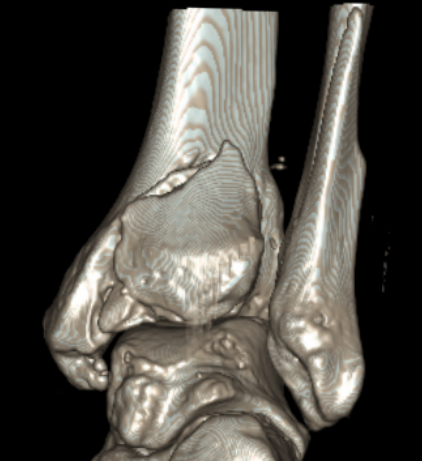

Mason and Malloy Classification

CT scan critical to classify and guide treatment / approach

| Type I | Type IIA | Type IIB | Type III |

|---|---|---|---|

| Avulsion of the PITFL |

Posterolateral fragment Volkmann fracture |

Posteromedial & posterolateral fragments Volkmann plus secondary fracture line |

Large coronal plane fragment Plafond fracture |